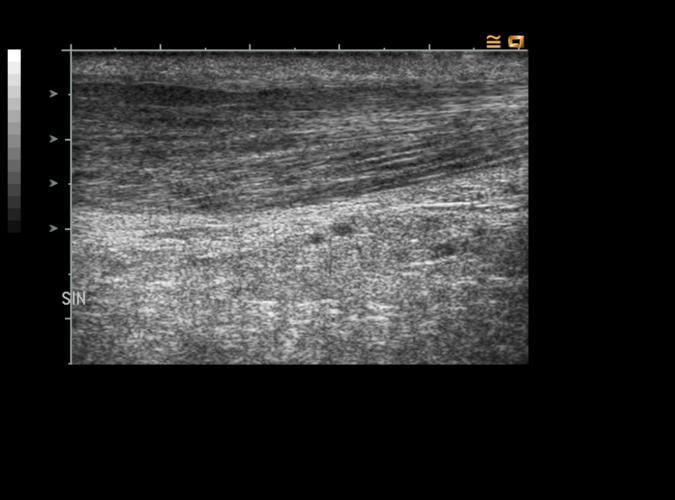

Patologi.

Long.vänster hälsena.

Kronisk tendinos/tendinit. se bild 9q